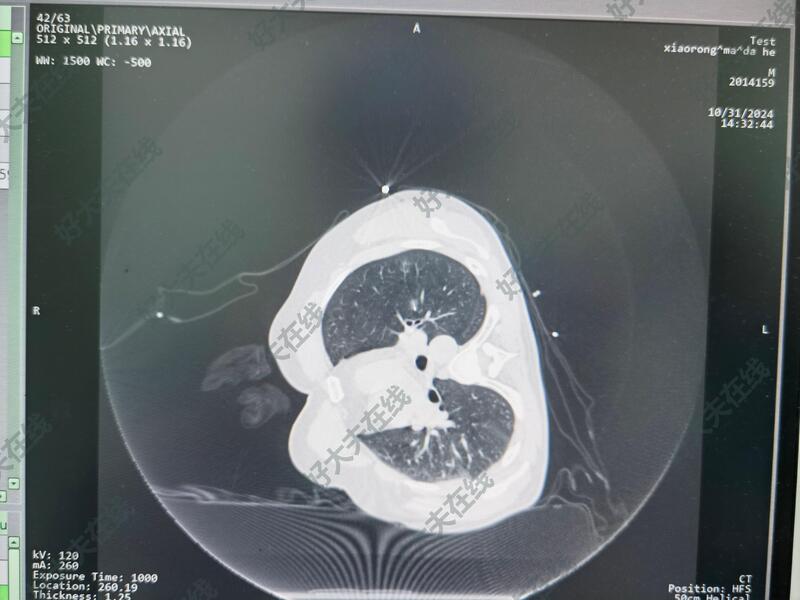

治疗前

肺部结节,CT考虑恶性可能性大,患者拒绝手术,充分了解治疗方案和消融手术治疗的利弊后决定行射频消融治疗。